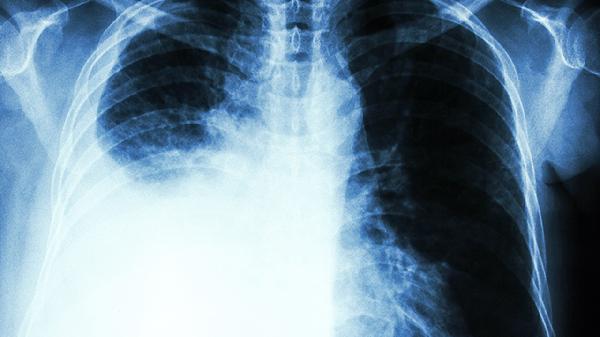

肺癌晚期的治疗原则是什么 了解肺癌晚期3个治疗原则

肺癌晚期治疗原则主要包括姑息治疗、全身治疗和对症支持治疗。姑息治疗以缓解症状为主,全身治疗通过药物控制肿瘤进展,对症支持治疗改善患者生活质量。